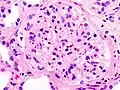

Гистопатологическая картина диабетического гломерулосклероза с нефротическим синдромом.